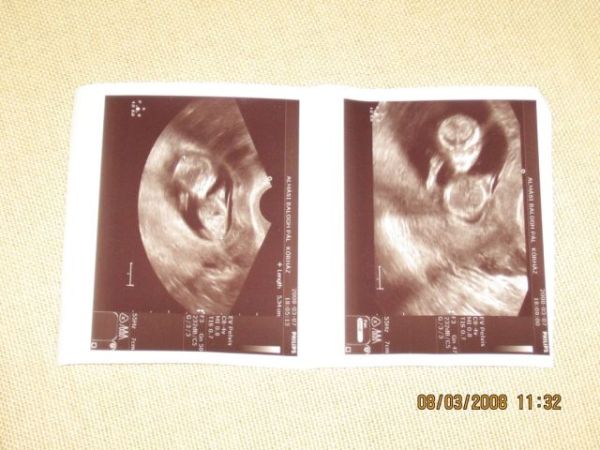

És ime a legifjabb családtagunk: :D Kép Kép

Na most rólunk is pár szót... :D

Tegnap megvolt az uh, és minden rendben az aprósággal. Tarkóredő 1,1mm, tökéletes. Kicsim meg produkálta magát (doki meg is jegyezte), úgy boxolt, mintha legyeket üldözne a pocimban. :D :D :D

Nagyon jó érzés volt, igazán sokáig feldobódtam tőle...